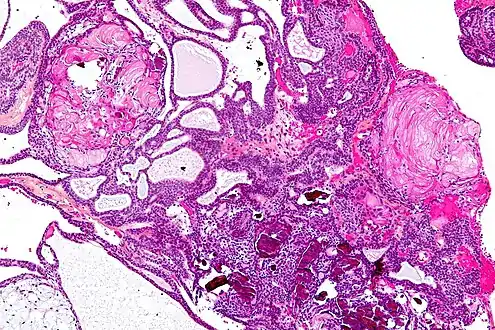

| Very low magnification micrograph of an adamantinomatous craniopharyngioma. HPS stain. | |

- Adamantinomatous craniopharyngiomas, which resemble ameloblastomas (the most common type of odontogenic tumor), are characterized by activating CTNNB1 mutations.

In the adamantinomatous type, calcifications are visible on neuroimaging and are helpful in diagnosis.

The papillary type rarely calcifies. A vast majority of craniopharyngiomas in children are adamantinomatous, whereas both subtypes are common in adults. Mixed-type tumors also occur.[25]

On macroscopic examination, craniopharyngiomas are cystic or partially cystic with solid areas. On light microscopy, the cysts are seen to be lined by stratified squamous epithelium. Keratin pearls may also be seen. The cysts are usually filled with a yellow, viscous fluid rich in cholesterol crystals. Of a long list of possible symptoms, the most common presentations include headaches, growth failure, and bitemporal hemianopsia.

Enhanced T1 weighted MRIs of craniopharyngiomas Micrograph showing the characteristic features of an adamantinomatous craniopharyngioma - cystic spaces, calcifications, and "wet" keratin, HPS stain